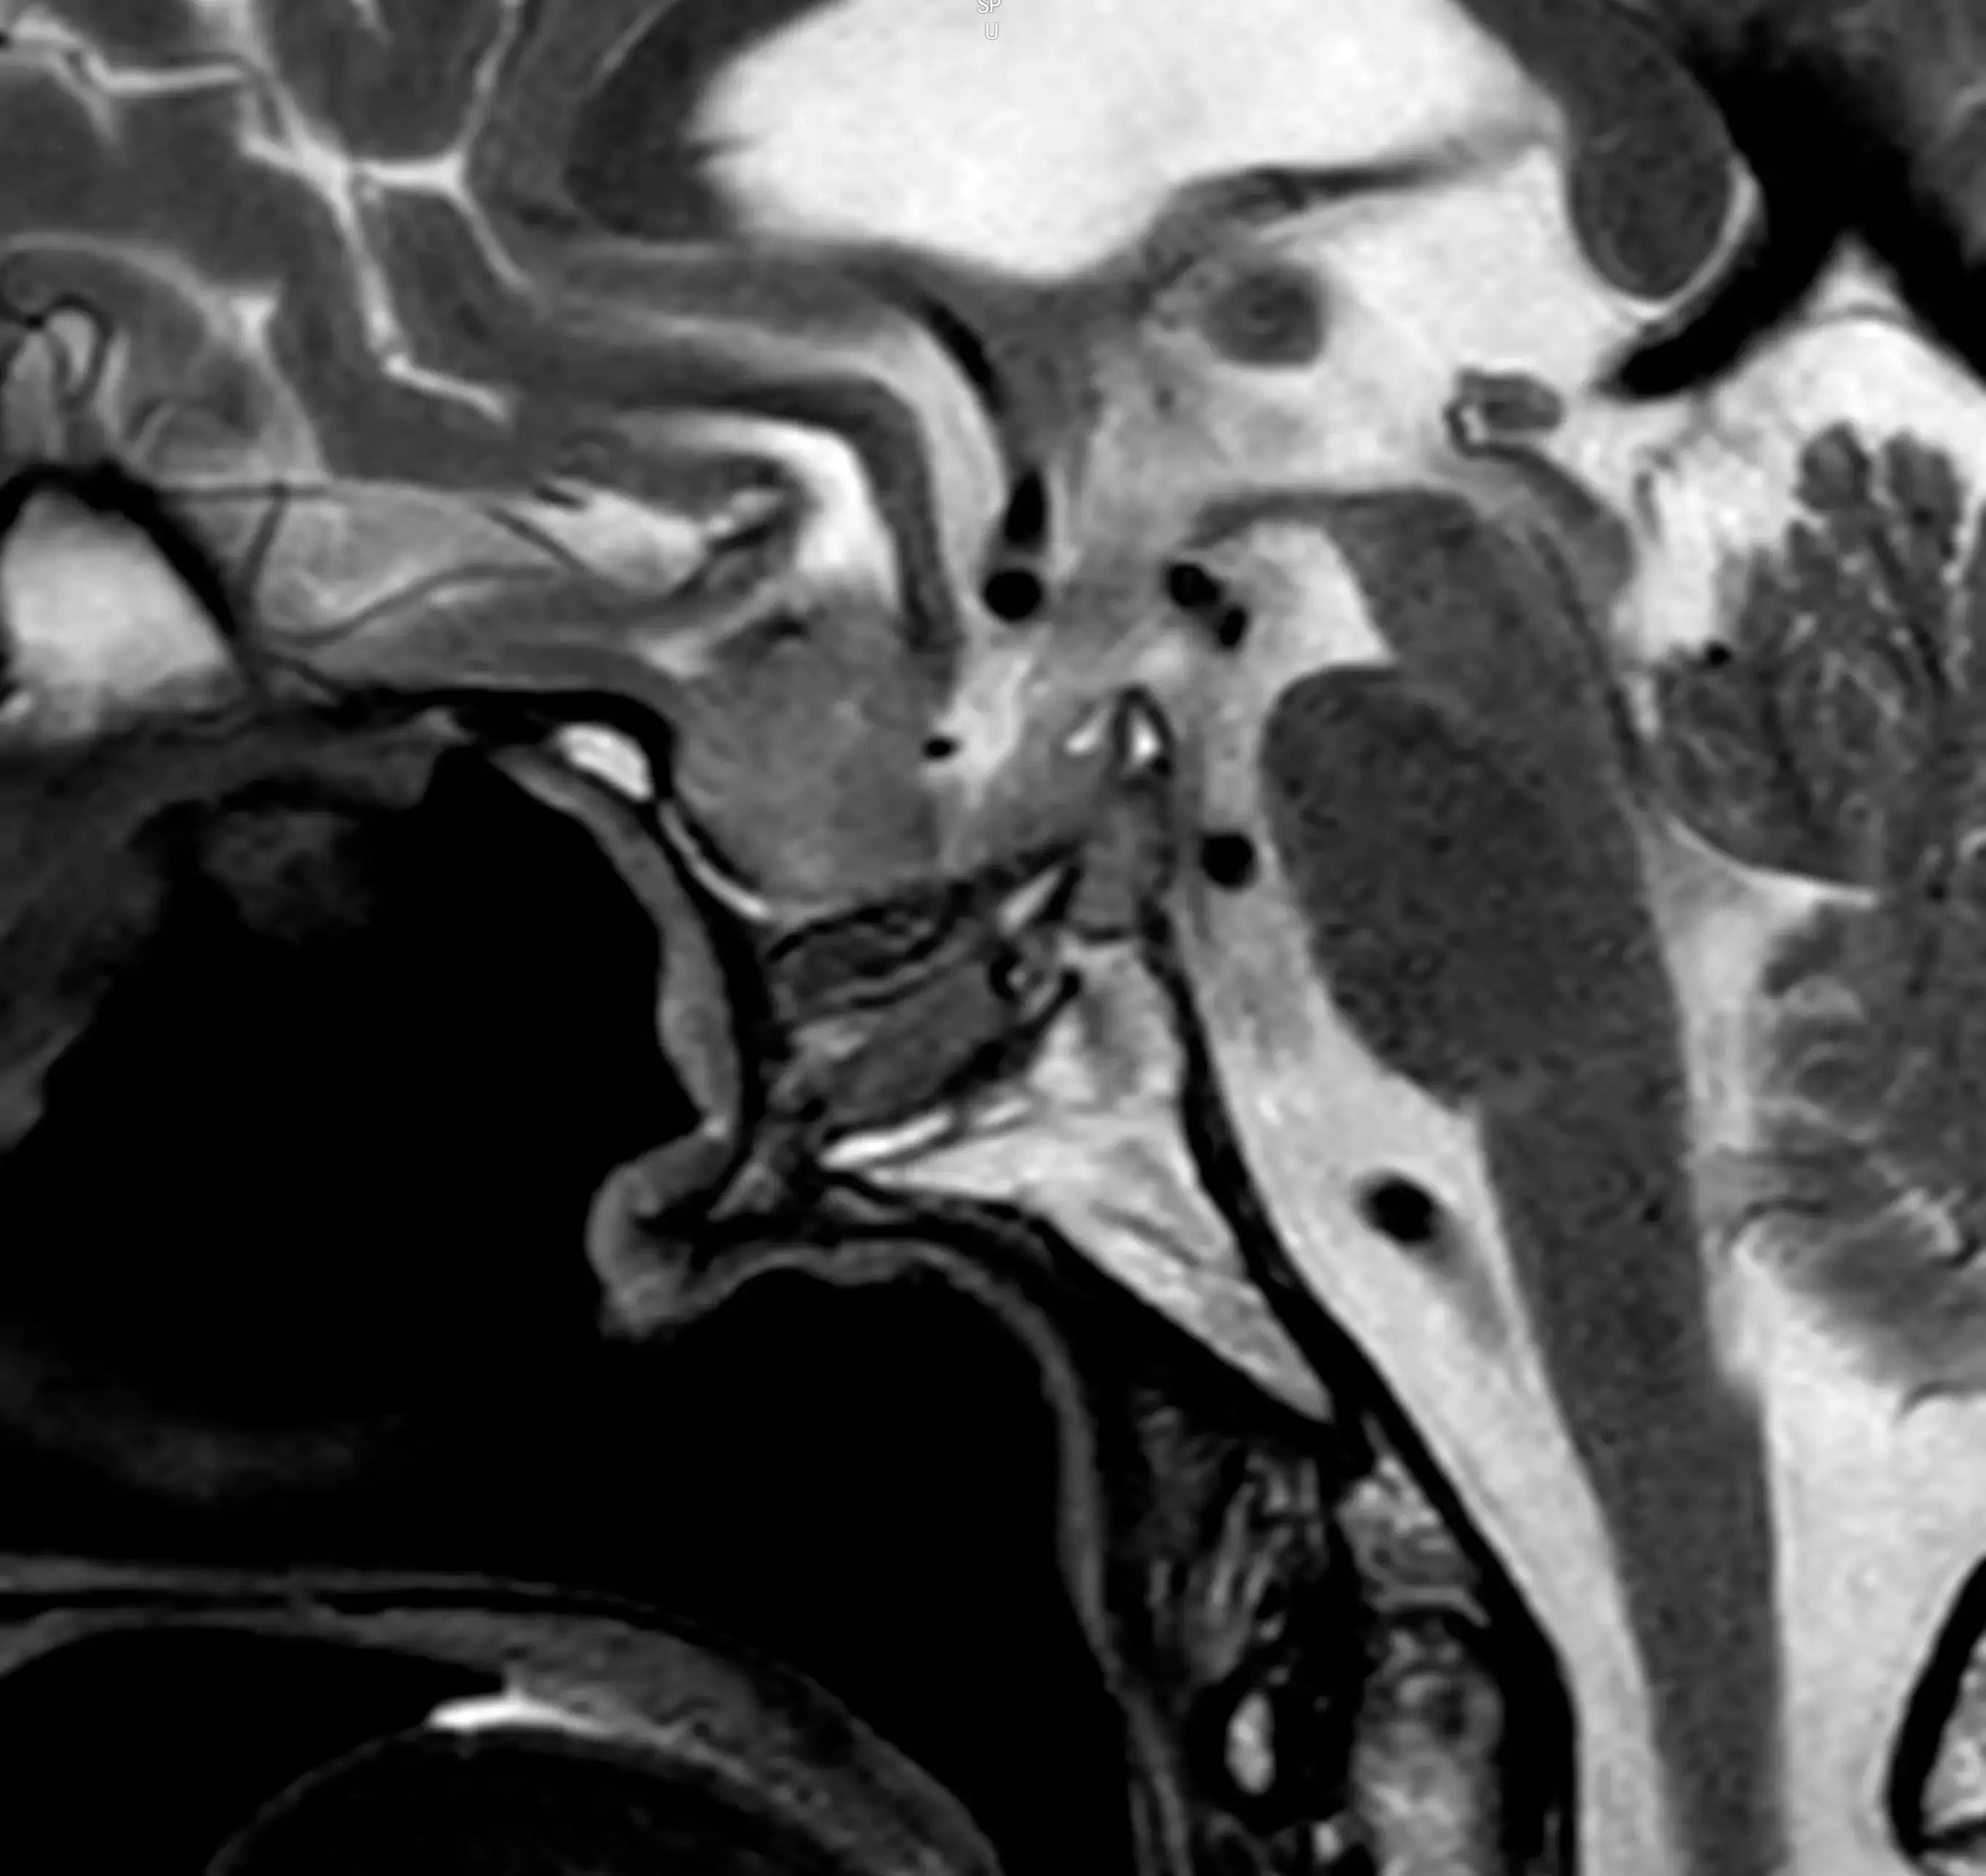

МРТ гіпофіза — це високоточне дослідження, яке дозволяє детально оцінити стан гіпофіза — невеликої, але дуже важливої залози головного мозку, що відповідає за регуляцію гормональної системи організму.

Обстеження проводиться за допомогою магнітно-резонансної томографії, яка дозволяє отримати детальні зображення тканин без використання рентгенівського випромінювання.

Що показує МРТ гіпофіза

Обстеження дозволяє виявити:

- аденому гіпофіза

- мікроаденому

- пухлини області турецького сідла

МРТ є найбільш інформативним методом для діагностики патологій гіпофіза.